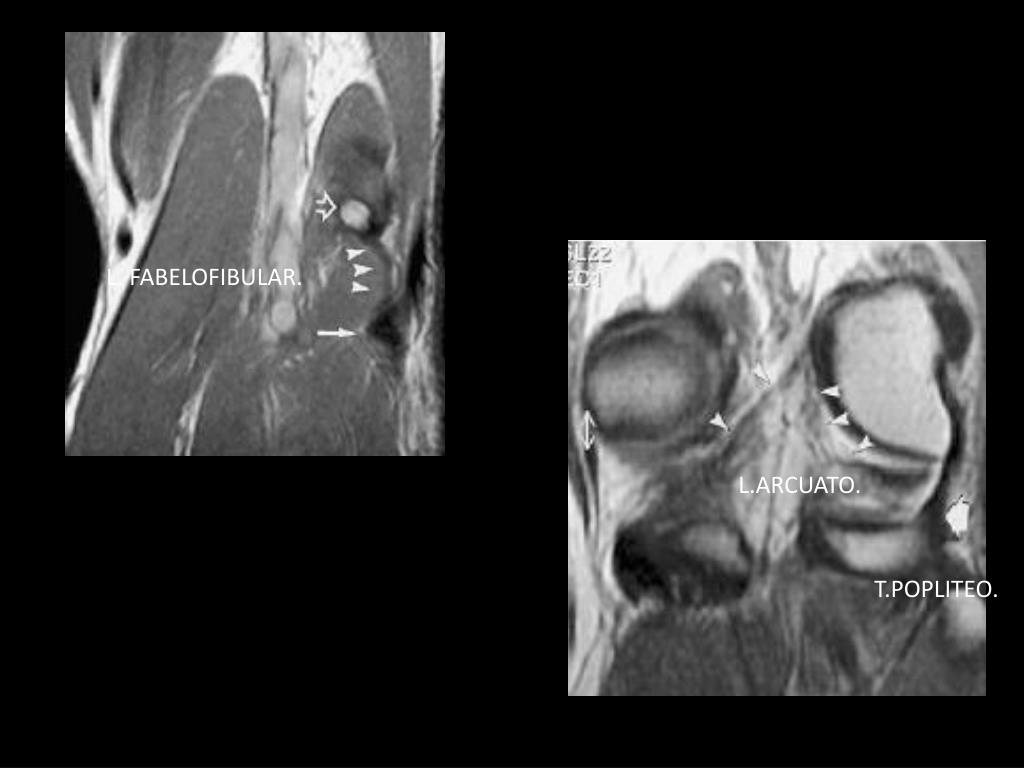

11. L. FABELOFIBULAR. L.ARCUATO. T.POPLITEO.